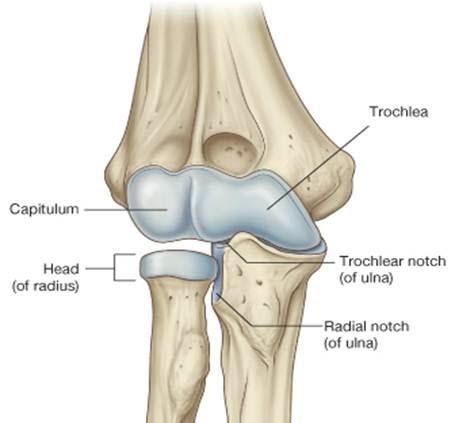

Describe the articulating surfaces of the elbow

Which other joint is also found within the joint capsule of the elbow?

Proximal radioulnar joint